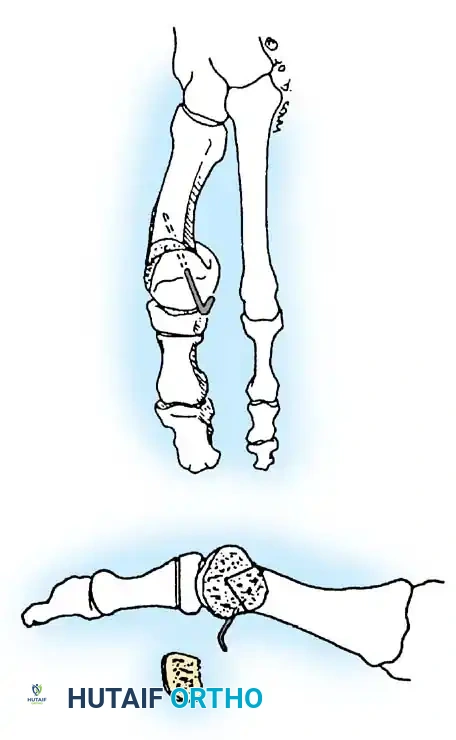

Hallux valgus (lateral deviation of the great toe) is not a single disorder, as the name implies, but a complex deformity of the fi rst ray that frequently is accompanied by deformity and symptoms in the lesser toes (Fig. 78-1). Often the angle between the fi rst and second metatarsals is more than the 8 to 9 degrees usually considered to be the upper limits of normal. The valgus angle of the fi rst metatarsophalangeal joint also is more than the 15 to 20 degrees considered to be the upper limits of normal (Fig. 78-2). If the valgus angle of the fi rst metatarsophalangeal joint exceeds 30 to 35 degrees, pronation of the great toe usually results. With this abnormal rotation, the abductor hallucis, which is normally plantar to the fl exion-extension axis of the fi rst metatarsophalangeal joint, moves further plantarward (Fig. 78-3). In this case, the only restraining medial structure is the medial capsular ligament with its capsulosesamoid portion (inserting into the base of the proximal phalanx) (Fig. 78-4) and capsulophalangeal portion (inserting into the plantar plate). The adductor hallucis, which is unopposed by the abductor hallucis, pulls the great toe further into valgus, stretching the medial capsular ligament (particularly the capsulosesamoid), attenuating this structure, and allowing the metatarsal head to drift medially from the sesamoids. In addition, the fl exor hallucis brevis, fl exor hallucis longus, adductor hallucis, and extensor hallucis longus increase the valgus moment at the metatarsophalangeal joint, further deforming the fi rst ray. The deep transverse intermetatarsal ligament runs between the plantar plates at the metatarsophalangeal joints and does not insert into bone on the adjacent sides of the metatarsal heads. Finally, the sesamoid ridge on the plantar surface of the fi rst metatarsal head (the crista) fl attens because of pressure (abutment) from the tibial sesamoid (Fig. 78-5). With this restraint lost, the fi bular sesamoid displaces partially or completely into the fi rst intermetatarsal space (see Fig. 78-2). In this situation, the patient is bearing less weight on the fi rst ray and more on the lesser metatarsal heads, increasing the likelihood of transfer metatarsalgia, callosities, and stress fracture of a lesser metatarsal.

Fig. 78-2 Hallux valgus complex. Note increase in intermetatarsal angle, lateral dislocation of sesamoids, subluxation of fi rst metatarsophalangeal joint (leaving metatarsal head uncovered), and pronation of great toe associated with marked hallux valgus.

Fig. 78-3 Pronation of hallux. A, Normal. B, Note plantar shift of abductor hallucis and lateral shift of sesamoids with associated intrinsic muscles of hallux. (Redrawn from Miller J: Acquired hallux varus a preventable and correctable disorder, J Bone Joint Surg 57A:183, 1975.)

Fig. 78-4 Anatomy of medial capsular ligament. Note accessory portion of medial capsular ligament inserting into tibial sesamoid and cord portion inserting into base of proximal phalanx plantar to longitudinal axis of fi rst ray. (Redrawn from Haines R, McDougall A: The anatomy of hallux valgus, J Bone Joint Surg 36B:272, 1954.)

Fig. 78-5 A, Plantar surface of fi rst metatarsal head. Entire sesamoid sling with attached intrinsic musculature has been rotated distally off metatarsal head to present schematically relationships of muscle, tendon, capsule, ligaments, and articular confi guration of fi rst metatarsophalangeal joint. B, As metatarsal head moves medially, sesamoid sling apparatus becomes valgus deforming force, and metatarsal rotates (pronates) on its longitudinal axis. Intrinsic and extrinsic muscle balance is lost, and deformity increases. ( A after Beverly Kessler; courtesy of LTI Medica and The Upjohn Company.)